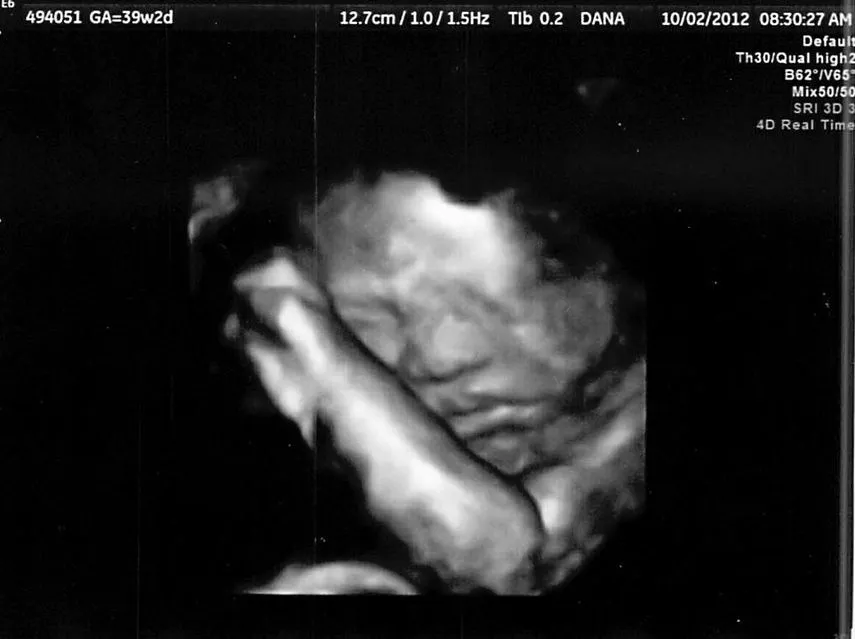

1. Thai nhi 39 tuần phát triển như thế nào?

Nếu bạn đang mang thai ở tuần thứ 39 thì bạn đang ở tháng thứ 9 của thai kỳ. Em bé khi được 39 tuần tuổi sẽ có kích thước tương đương với một quả dưa hấu nhỏ.

- Cân nặng: 2,905 – 3,897kg.

- Chiều dài: tính từ đầu đến gót chân dài khoảng 50,7cm.

Ngoài ra, dấu hiệu thai 39 tuần khỏe mạnh còn gồm các chỉ số sau:

- Đường kính lưỡng đỉnh (BPD): 85 –101mm

- Chu vi vòng đầu (HC): 313 – 359mm

- Chiều dài xương đùi (FL): 67 – 79mm

- Chu vi vòng bụng (AC): 309 – 392 mm

Sự phát triển của thai nhi 39 tuần

- Trọng lượng cơ thể của bé dần dần chững lại.

- Tóc của thai nhi 39 tuần đã mọc nhanh và nhiều hơn.

- Lớp sáp bao phủ làn da và lớp lông tơ đã được thay bằng lớp da non.

- Móng tay, móng chân mọc đầy đủ, phủ được phần đầu các ngón tay và ngón chân của bé.

- Các cơ quan như não và phổi của bé đã tương đối hoàn chỉnh và vẫn đang tiếp tục phát triển.

- Hiện tượng dây rốn quấn quanh cổ (ít phổ biến): Hiện tượng này tương đối bình thường, tuy nhiên bác sĩ sẽ yêu cầu mẹ sinh mổ nếu dây rốn quá ngắn hoặc dây rốn bị chèn ép khiến cho nguồn oxy cung cấp bị giới hạn.